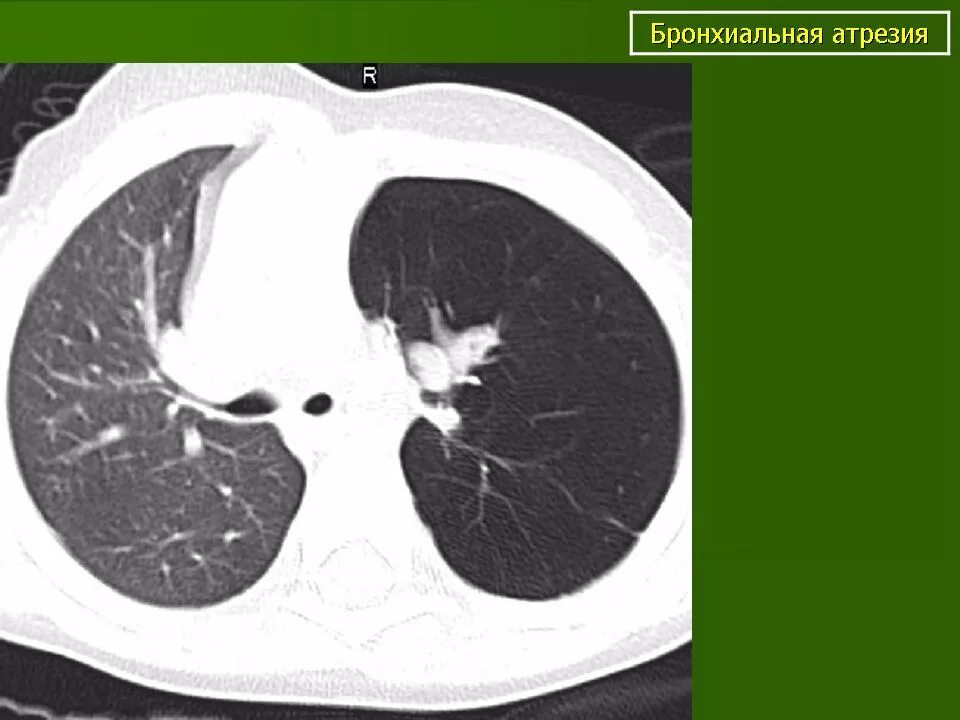

Утолщение бронха